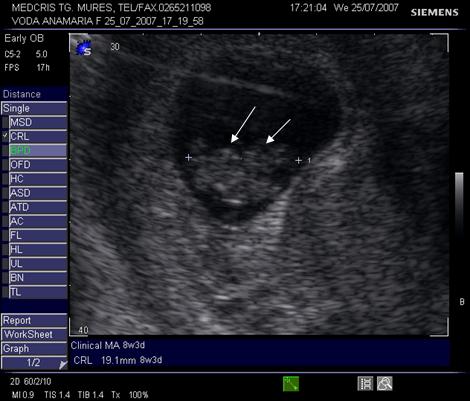

Fig. nr. 15. Sarcina 8 sapt, aparitia veziculei telencefalice anecogene in extremitatea cefalica ( sageata )